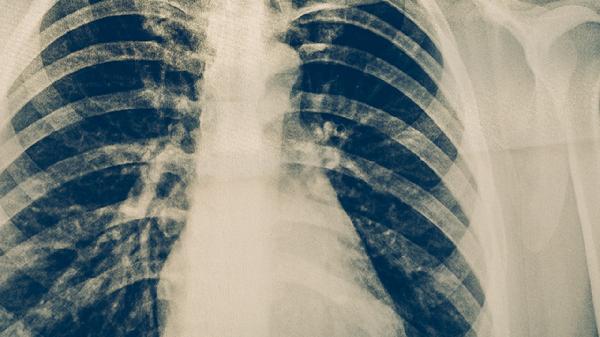

肺结核通常需要遵医嘱使用异烟肼片、利福平胶囊、吡嗪酰胺片、乙胺丁醇片、链霉素注射液等抗结核药物。肺结核是由结核分枝杆菌感染引起的慢性传染病,需规范联合用药以减少耐药性。

肺结核患者需严格遵循早期、联合、适量、规律、全程的用药原则,完成6-9个月的标准疗程。治疗期间保持高蛋白饮食如鸡蛋、瘦肉,适当补充维生素A和D。注意隔离措施,咳嗽时掩住口鼻,定期进行痰菌检查和胸部影像学复查。出现药物不良反应或症状加重时需及时复诊调整方案。